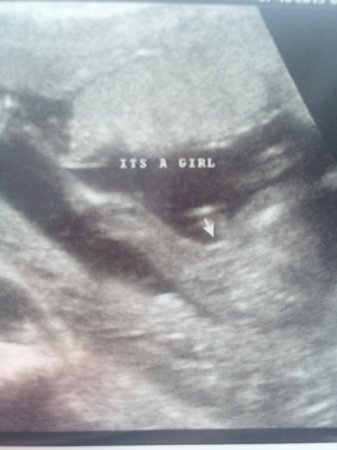

I don't see any gender clues. Sorry!

What gestation is this?

Feelings don't predict gender accurately and the tech sees a lot during the scan far beyond what we see on pictures. If the tech says it is a girl and you're far enough along in pregnancy to be accurate, then it is most likely a girl.